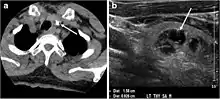

In medicine, nodules are small firm lumps, usually greater than 1 cm in diameter.[1][2] If filled with fluid they are referred to as cysts.[2] Smaller (less than 0.5 cm) raised soft tissue bumps may be termed papules.[3]

Nodules in skin include dermatofibroma[5] and pyogenic granuloma.[6] Nodules may form on tendons and muscles in response to injury,[7] and are frequently found on vocal cords.[8] They may occur in organs such as the lung,[9] or thyroid,[10] or be a sign in other medical conditions such as rheumatoid arthritis.[11]

Nodules are small firm lumps usually greater than 1 cm in diameter, found in skin and other organs.[1][2] If filled with fluid they are usually softer and referred to as cysts.[2] Smaller (less than 0.5 cm) raised soft tissue bumps may be termed papules.[3]

Often discovered unintentionally on a chest x-ray, a single nodule in the lung requires assessment to exclude cancer.[9]